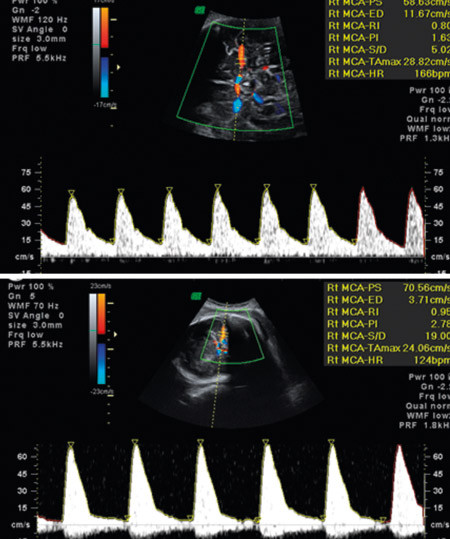

Figur 3  Dopplerundersøkelse av blodstrømshastighet i a. cerebri media ved uke 32 fra normalt foster (øverst) og anemisk…

Figur 3 Dopplerundersøkelse av blodstrømshastighet i a. cerebri media ved uke 32 fra normalt foster (øverst) og anemisk foster (nederst), med forhøyet systolisk maksimal strømningshastighet (> 1,5 g median verdi i forhold til svangerskapsalder)

Mot andre blodtypeimmuniseringer finnes det ikke profylakse. Alle gravide med klinisk betydningsfulle antistoffer trenger utredning og oppfølging for å identifisere fostre med risiko for å utvikle anemi. Det innebærer utredning av fosterets Rh-status ved hjelp av blodprøve av mor og gjentatte ultralydundersøkelser som inkluderer dopplermålinger (fig 3). Slik følges en ev. utvikling av fosteranemi, og man kan finne det gunstigste tidspunktet for ultralydveiledet intrauterin transfusjon. I postnatalperioden omfatter behandlingsmulighetene lysbehandling, immunmodulering med høydose intravenøst gammaglobulin og utskiftingstransfusjon. Tilgjengelig statistikk tilsier at det oppdages 50–60 nyimmuniseringer mot andre blodtypeantigener enn Rh(D) hos gravide per år (2). I tillegg kommer tilfeller av hemolytisk sykdom der mor har blodtype O og barnet blodtype A eller B og mors preformerte IgG anti-A eller anti-B gir hemolyse postnatalt (ABO-uforlikelighet).